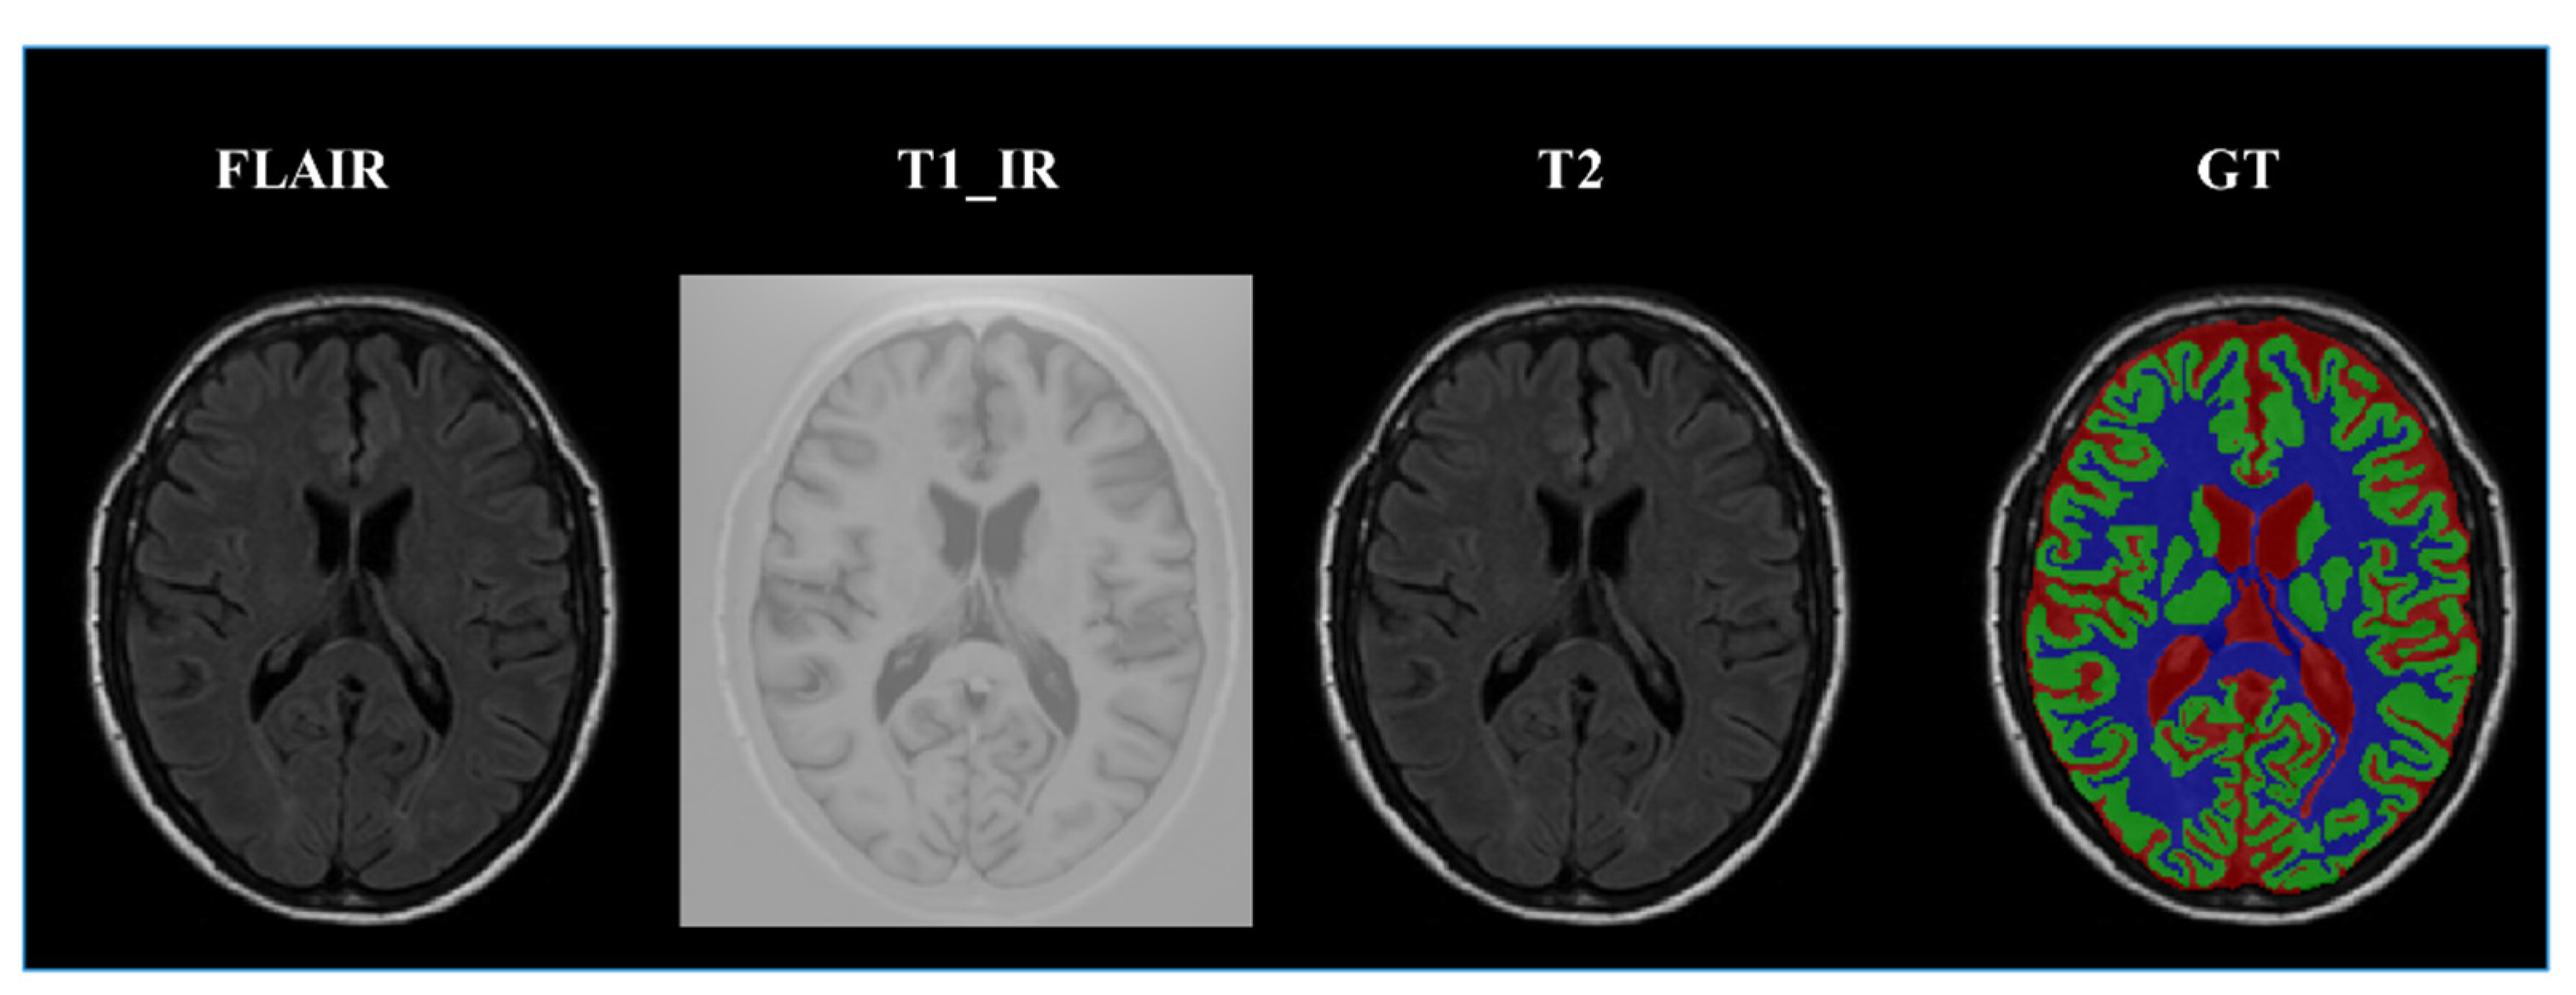

3.5. Dataset Introduction